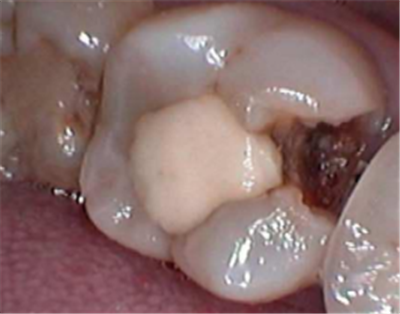

第一阶段(脱矿):细菌利用食物残渣(尤其是糖分)产生酸性物质,这些酸会慢慢腐蚀牙齿最外层的牙釉质。这个阶段,牙齿表面可能只是出现白色或褐色的斑点,但质地仍然完整,没有实际的“洞”。您通常没有任何感觉。

第二阶段(崩解):腐蚀持续进行,牙釉质这个坚硬的外壳终于支撑不住了,从内部开始坍塌。就像被虫子从内部蛀空的木头,表面看只有一个小点,但内部已经空了。当表面的牙釉质薄到一定程度,在一次正常的咀嚼或刷牙受力下,它就会突然破裂,形成一个您能明显感知到的“洞”。

很多龋病发生在牙齿的邻面(牙缝之间)或者后牙的窝沟深处,这些地方肉眼很难直接看到。只有当洞扩大到一定程度,您用舌头才能舔到,或者食物开始塞牙时,您才会“突然”发现它。